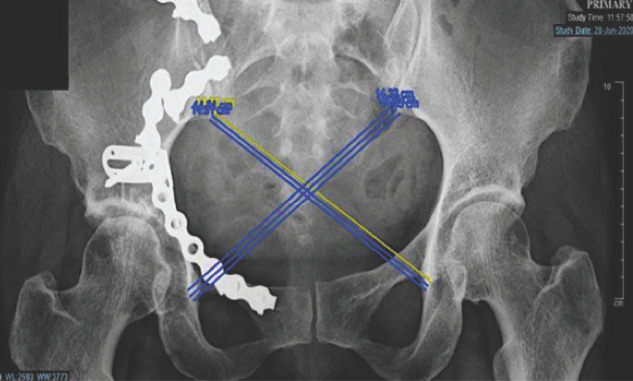

Material and methods: This retrospective study involved 15 patients with unstable pelvic injuries requiring surgical intervention from January 2015 to December 2020 who undergone anterior stabilisation of the sacroiliac joint. Radiological outcome assessments were done postoperatively by using Lindahl criteria. The complete functional outcome was assessed at least six months postoperatively when patients were able to weight bear by using Majeed system. Descriptive statistical analysis was performed using IBM SPSS Statistics Version 27.

Results: The participants consist of 73.3% male and 26.7% female patients. A total of 66.7% of patients had a Tile type B pelvic ring injury, and the remaining 33.3% had a Tile type C pelvic ring injury. Based on the Majeed system, 73.3% of patients had excellent functional outcomes, and based on Lindahl criteria; there were 60% of patients who had excellent radiological outcome. However, there was no significant agreement between functional and radiological outcomes.

Conclusion: Definitive fixation of the sacroiliac joint by anterior plate stabilisation provided an excellent functional and radiological outcome mainly due to good anatomical reduction and mechanical stability. However, further study may be needed to evaluate the correlation between functional and radiological outcomes and compare the various method of fixation with a larger sample size.